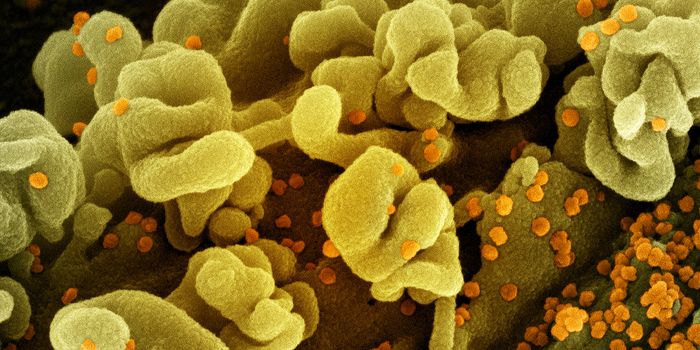

MAY 23, 2020MicrobiologyThe massive demand for diagnostic testing led the FDA to open a short window for many testing products to go to market w ...

JUN 08, 2020MicrobiologyDiagnostic tests have recently been getting a lot of attention because of the COVID-19 pandemic.

SEP 17, 2018MicrobiologyEvidence mounts that viruses play a role in disease development.